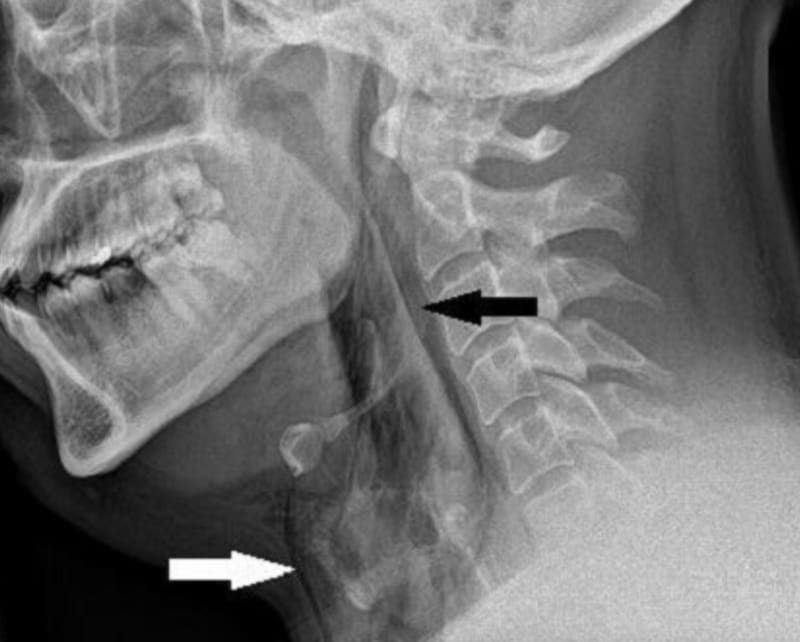

Tras hacerle una radiografía, los doctores descubrieron que el paciente había sufrido un desgarro de 2 mm en su tráquea. Los cirujanos cardiotorácicos del Hospital Ninewells consideraron que no era necesario realizar una operación, puesto que el hombre “se encontraba sistémicamente bien con frecuencia cardíaca y respiratoria normal”, detalla la revista.

Después de cinco semanas el desgarro del paciente logró sanar, según mostraron las radiografías.